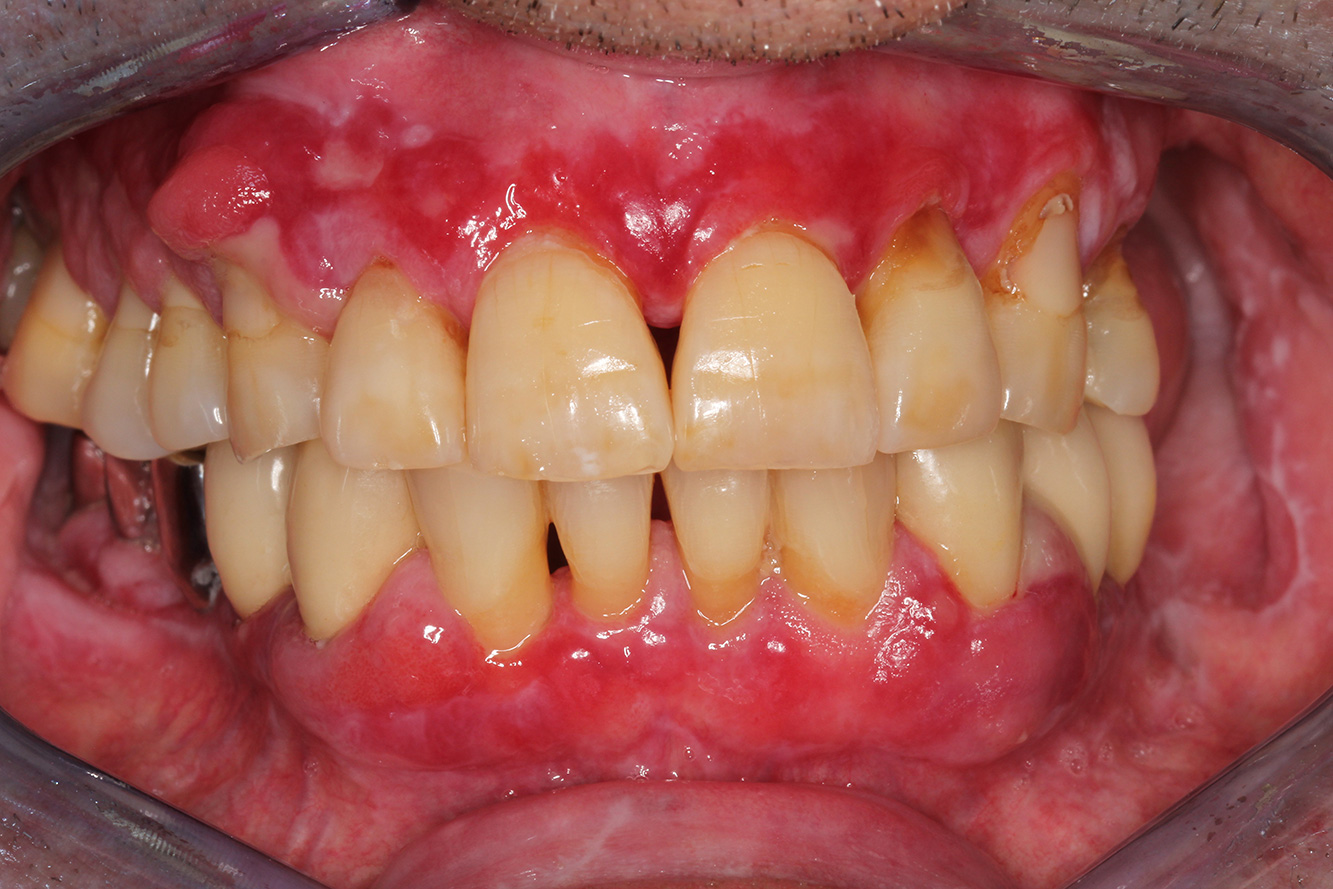

Ein 71-jähriger Patient mit Z.n. Nierentransplantation und Hypertonie (Bluthochdruck) stellt sich vor. Bedingt durch die Krankengeschichte ist eine Dauermedikation mit Cyclosporin, zur Unterdrückung der Immunabwehr, und Amlodipin, zur Blutdrucksenkung, erforderlich. Außerdem berichtet der Patient über empfindliches Zahnfleisch und Zahnfleischbluten. Aus mundgesundheitlicher Sicht zeigt sich ein saniertes Gebiss mit acht fehlenden Zähnen, ausgeprägte Gingivawucherungen, eine Parodontitis Stadium II, Grad B mit aktiven Taschen und eine initiale Wurzelkaries an Zahn 22. In der Kariesrisikoabschätzung wird ein mittleres Kariesrisiko (API 60) festgestellt. Für die Prophylaxesitzung lassen sich folgende Behandlungsempfehlungen ableiten.

Anhand der Krankengeschichte lässt sich ein besonderes Komplikationsrisiko erkennen. Aufgrund des Nierentransplantats ist der Patient immunsupprimiert (Cyclosporin), verfügt also über ein geschwächtes Immunsystem und benötigt eine Infektionsprophylaxe (Empfehlung: 2 g Amoxicillin als Antibiotikum 1h vor Sitzung). Gleichzeitig birgt die Dauermedikation des Patienten ein erhöhtes Erkrankungsrisiko, da die festgestellten Gingivawucherungen medikamentenassoziiert sind (21).

Besonders im Bereich der Motivation und Instruktion muss auf die Situation des Patienten eingegangen werden. Durch die Gingivawucherungen gestaltet sich die häusliche Mundhygiene schwierig. Die erhöhte Anfälligkeit für Infektionen sowie das Fortschreiten und die Neuentstehung der Wucherungen (22) sollte auf Augenhöhe thematisiert werden. Gleichzeitig müssen die individuell auf den Bedarf abgestimmten Hygienetechniken vermittelt werden.

Für den Patienten ist ein verkürztes Recall-Intervall von drei bis vier Monaten zu empfehlen. Dieses beruht hauptsächlich auf den medikamenten-assoziierten Gingivawucherungen, der damit einhergehenden erschwerten Pflegesituation und dem Progressionsrisiko der Parodontitis.